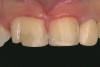

Fig 1 and Fig 2. Pretreatment photographs. Patient at 9 years of age on presentation.

A 9-year-old girl, referred to a prosthodontic office by her pediatric dentist, presented with her mother’s chief complaint: “The kids are teasing her about her big front tooth.” Findings from radiographic and clinical examinations revealed fused maxillary central-peg lateral incisors, teeth Nos. 7 and 8, and a congenitally missing lateral incisor, tooth No. 10 (Figure 1 through Figure 3). An implant was selected as the ideal treatment to replace tooth No. 10 when somatic growth was complete. A diagnostic wax-up was fabricated to determine if the fused tooth could be made to resemble two teeth, using pink composite to give the illusion of an interproximal papilla. The patient was referred for an orthodontic consultation to plan for closure of the diastema between teeth Nos. 8 and 9 and achievement of proper alignment for implant No. 10. The patient was also referred to a periodontist for pretreatment assessment of the tooth No. 10 site. An endodontist was consulted should exposure of the large pulp occur during tooth preparation.